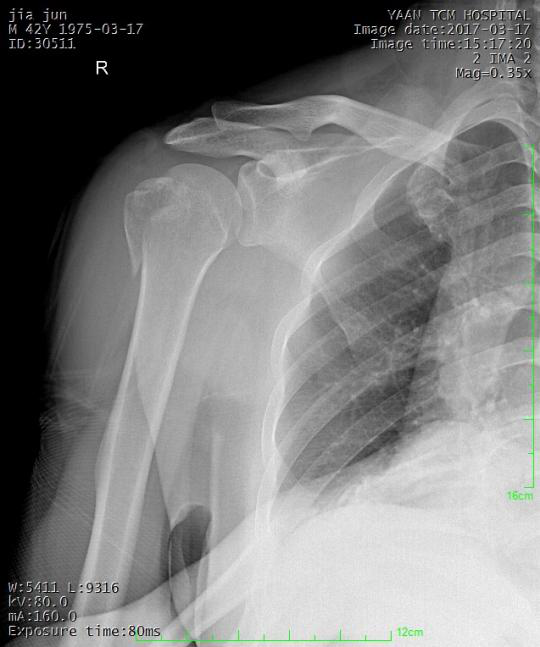

常见骨折手法整复:

桡骨下端骨折

术后